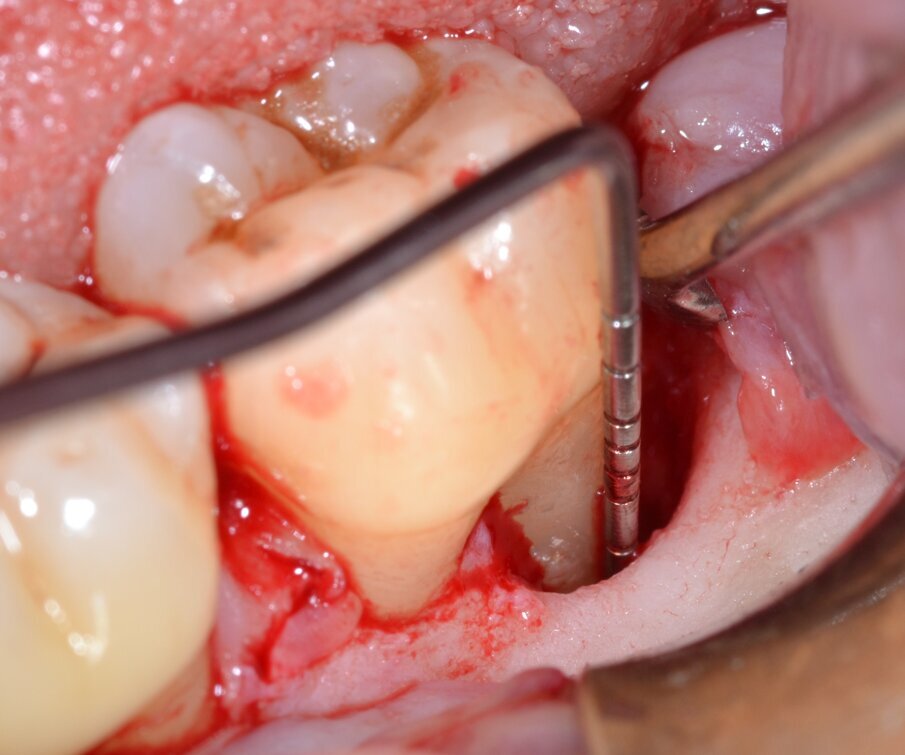

Dopo analgesia locale ottenuta per infiltrazione di Articaina cloridrato 40 mg con epinefrina 1:100.000 viene effettuata l’incisione di accesso secondo la tecnica denominata “Crestal Incision”4 per elevare un lembo a spessore totale che espone l’area interessata dal difetto (Fig. 5). Il debridement e la decontaminazione della superficie radicolare vengono effettuati per mezzo di inserti ultrasonici dedicati (Figg. 6, 7); al completamento di questo tempo chirurgico il difetto è innestato con biomateriale eterologo protetto da una membrana di tipo riassorbibile in pericardio di origine animale che viene fissata sulla cresta ossea mediante pins in titanio allo scopo di stabilizzare il coagulo e guidare la rigenerazione tissutale all’ interno del difetto. La ferita chirurgica è suturata con un filo riassorbibile 6/0 in PGA (Figg. 8-12).

Fig. 5 - Sondaggio della componente intraossea del difetto.